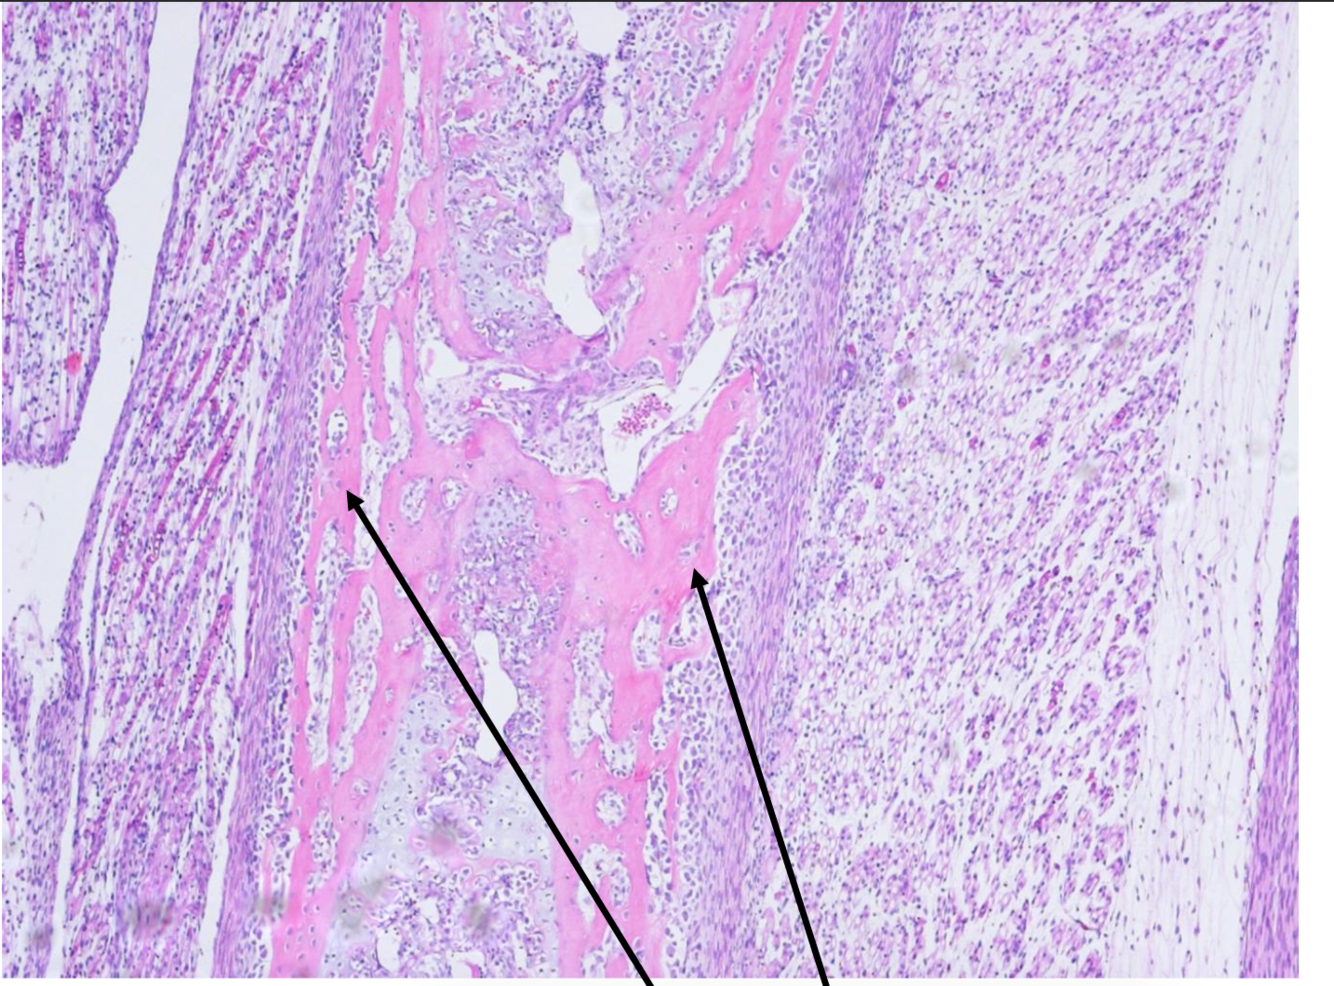

A) Old bone B) Cartilage C) Soft Callus D) Fracture site